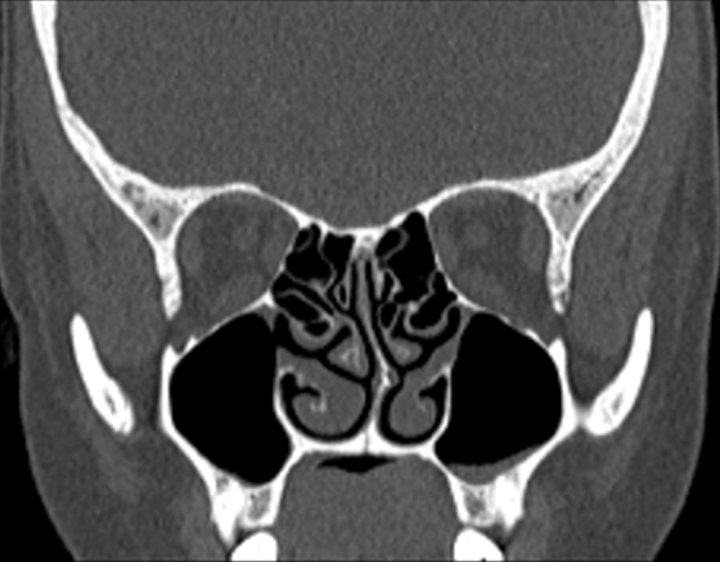

Click any image for labels.